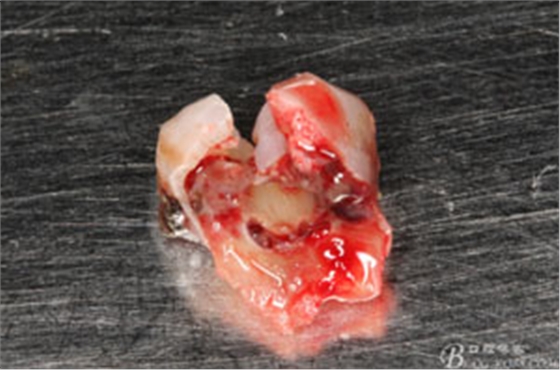

圖7.37牙冠碎裂。多生牙壓迫吸收程度嚴(yán)重。

圖8.拔除的37頰側(cè)的牙根完全被壓迫吸收完

圖4.術(shù)后拔除的牙根: